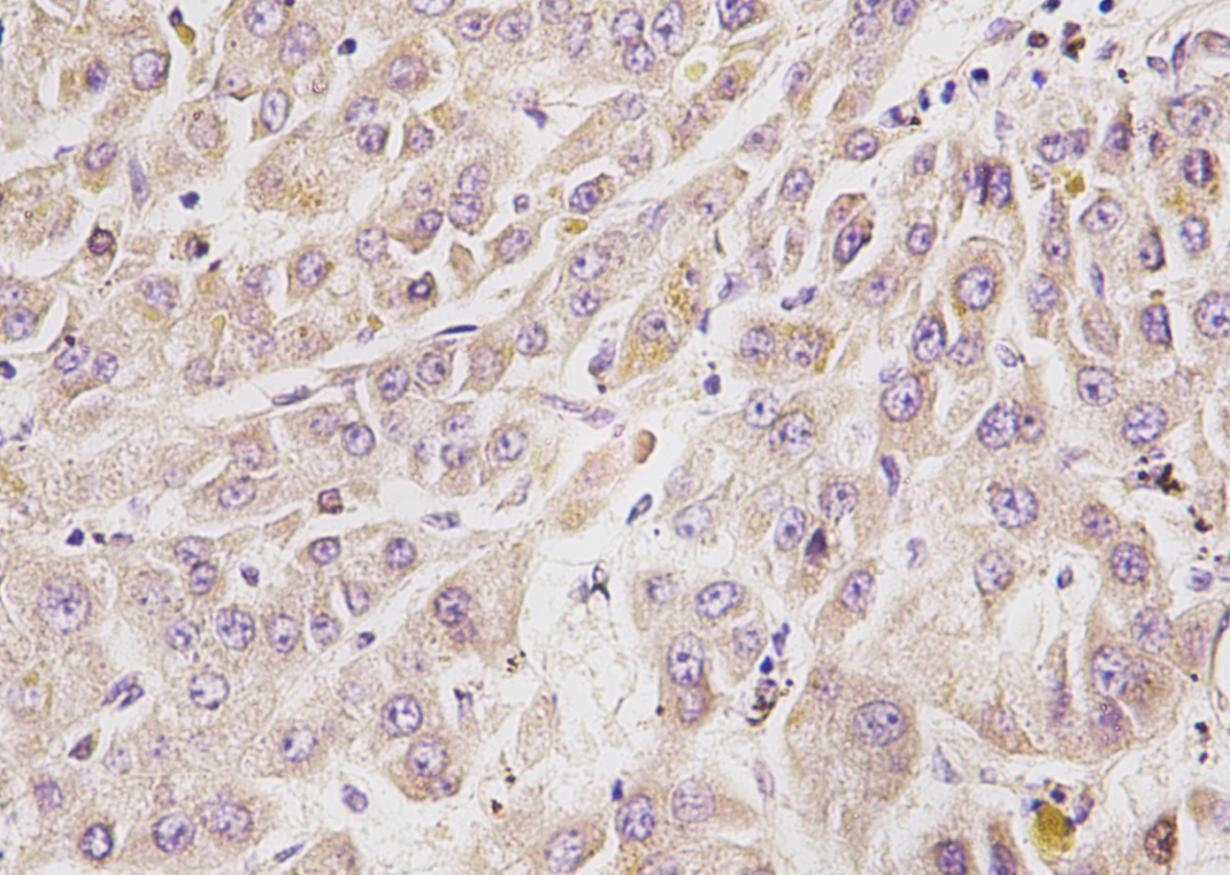

Calretinin

Calretinin是一种钙结合蛋白,为EF手蛋白家族成员之一,其功能可能是缓冲细胞内钙离子,在听觉神经元中含量丰富。可在视网膜、小脑、结肠等部位表达。

| 细胞定位 | 细胞质/核 |